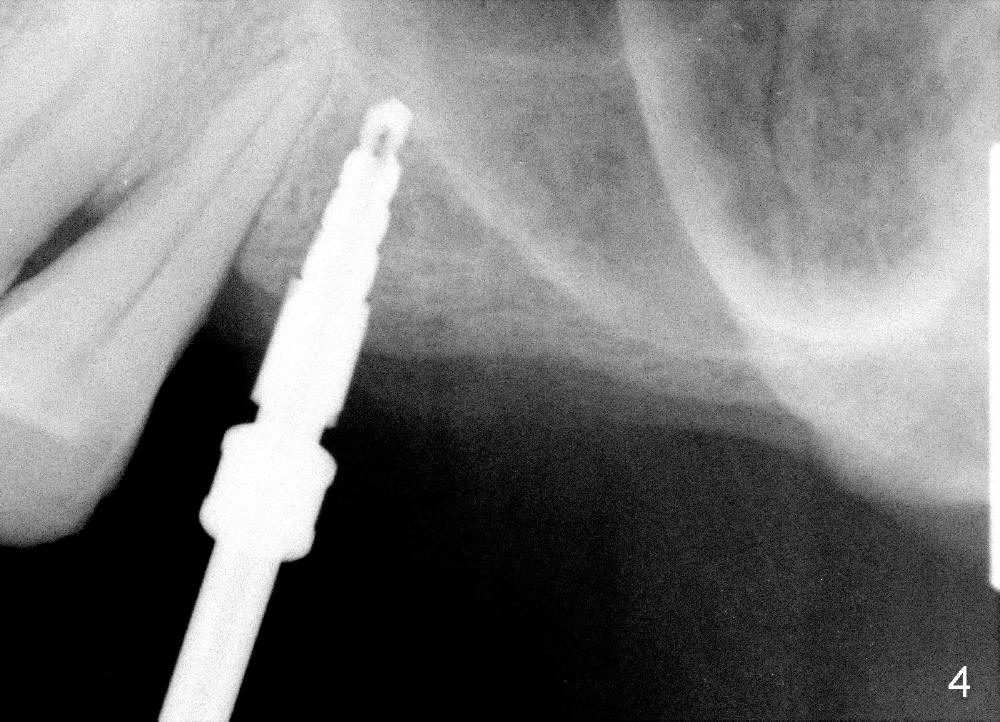

CT analysis (Hounsfield units) shows D2/3 bone at the site of #13. Osteotomy is created by using drills. Fig.4 shows 3.5 mm drill at the depth of 8 mm. The trajectory needs to be adjusted. When 4 mm drill is done, the osteotomy is ovoid in shape. The implant should be 4 or 4.5 mm?

To solve the dilemma, 4.5x11 mm tap is placed by a wrench at the depth of 8

mm. So an adapter is required. Hand placement of the tap is more

controllable than handpiece's in term of trajectory (Fig.5, 5'). Although hand

placement of the tap is slower, it gives us time to watch whether the buccal

plate is fracturing or not. The depth is also controlled better